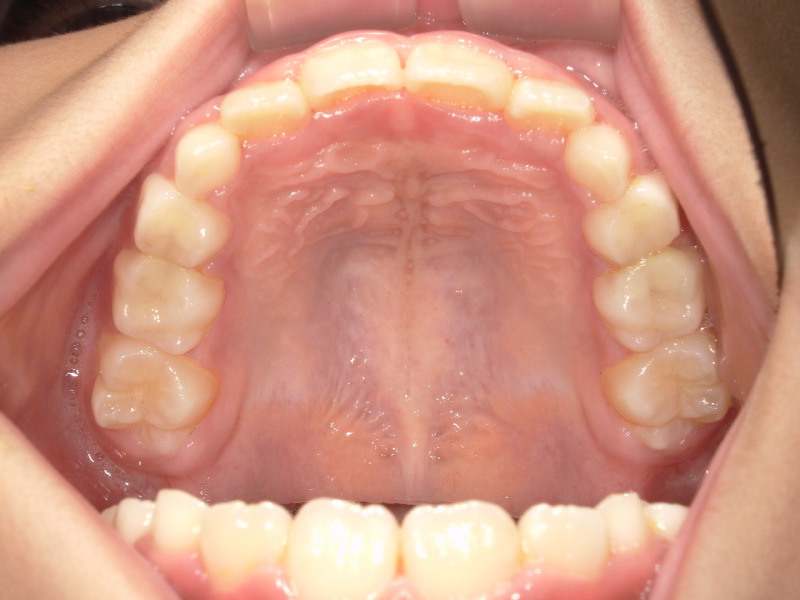

歯並びも良くなってきていますが、まだアーチは完全なUの字にはなっていません。

そのため舌のお手伝いをしてくれる装置を一時的に入れました。

最初は少し違和感はありますが、すぐに慣れる子が多いです。

3ヶ月頃で外すのですが、しっかり前歯が並んできています。

ですがまだ3番目の歯が入る余裕はない状態です。